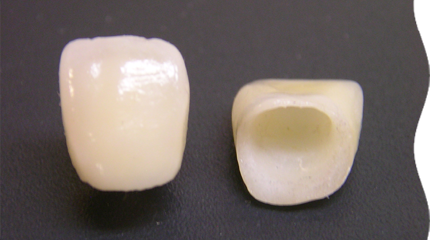

オールセラミック

全てセラミックでできており、金属を使用していないため金属アレルギーの方も安心です。

最も天然歯に近い色を出すことができ、審美性が高く前歯や小臼歯にも使われることが多い素材です。

ジルコニア

ジルコニアは頑丈で、白く透明感もあるので目立ちにくいのが特長です。

変色しにくく、ブリッジなどにも幅広く使える万能な素材です。

メタルボンド

外側にセラミックを使用し、内側を金属で補強しています。

強度に優れ、耐久性があることが特長で、奥歯の噛む力が強い方やブリッジも安心して使用できます。